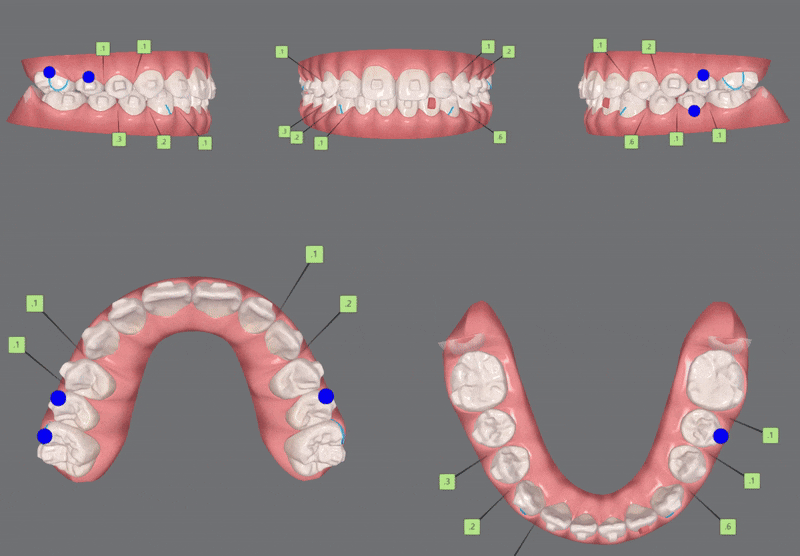

1st ClinCheck(30개)

첫번째 클린체크의 영상입니다.

인비절라인의 장점 중의 하나는

교정 후의 모습을 예측할 수 있는것 입니다.

원장님께서 클린체크 디자인을 마치게 되면

인비절라인 교정치료 후에

치아이동이 어떻게 변화하는지 클린체크를 통해 확인 해 볼 수 있는것인데요.

첫번째 클린체크에서는 총 30개의 장치로

진행 해드렸습니다.

인비절라인 첫번째 클린체크 30개의 장치로

치아끼리 맞닿고 있던 앞니들이

개선되면서

윗니가 아랫니를 덮는 정상에 가까운 교합 상태로 개선되었습니다.

2nd ClinCheck(18개)

두번째 클린체크는

첫번째 클린체크에 추가적으로 어태치먼트를 부착하여 18개의 장치로

치아배열을 개선시켜 주었습니다.

이전의 클린체크와는 어태치먼트의 모양과 위치가

달라져

이전의 클린체크를 보완해 교정치료의 완성도를 높여 줍니다.